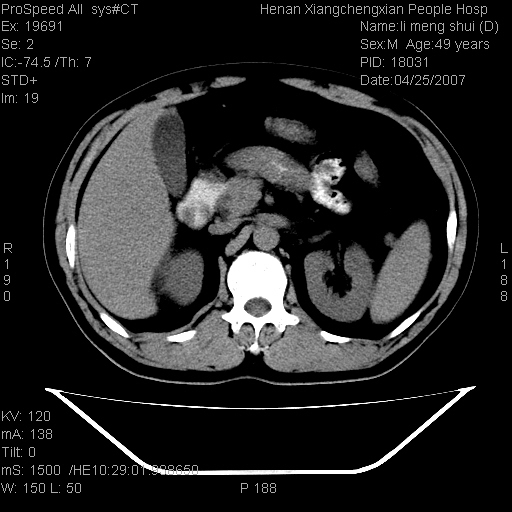

| 患者,男,49岁, 腹疼伴恶心\\呕吐20天,20天前无明显诱因出现右上腹部疼痛,钝疼,无放射,伴恶心\\呕吐,不伴发热.患者不愿增强. b超:肝脏右叶实性占位. ct:肝脏右叶可见一巨块状圆形低密度影,大小约93mm*84mm,其内可见点状高密度影,胆囊、胰腺、脾脏大小、形态及密度未见异常,腹膜后间隙未见肿大淋巴结影。 印象:肝脏右叶巨大肿块,性质待定,建议增强并穿刺活检进一步确诊。 ct平扫: ![]() ![]() ![]() ![]() ![]() ![]() ![]() ![]() ![]() ![]() ![]() ![]() ![]() ![]() ![]() ![]() ![]() 肝脏右叶肿块ct引导下穿刺活检术 患者于16时05分仰卧于ct检查台上,首先行肝脏ct扫描确定进针位置、深度、角度。在局麻下行ct引导下肝脏右叶肿块穿刺活检术。常规消毒、铺巾、局麻。在ct引导下使活检针经右侧腋中线、第9肋间隙垂直胸壁进针90mm,针头进入病变预定位置。在病变预定位置多点、多方向抽取小米样病变组织多块,涂片五张送病理检查。术后穿刺点局部无出血,未出现腹腔积液等并发症。术中及术后患者生命体征稳定,手术于17时10分成功完成。患者安返病房。 穿刺片 ![]() ![]() ![]() ![]() ![]() ![]() ![]() ![]() ![]() ![]() ![]() ![]() ![]() ![]() ![]() ![]() 病理结果肝细胞癌 ![]() 原贴地址:http://www.radinet.com.cn/forum_view.asp?forum_id=4&view_id=24130 ok |